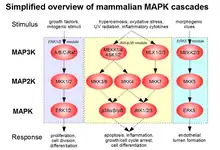

Genetic studies show that specific gene mutations or deletions are causes for the disease. The genes identified for cerebral cavernous hemangiomas (or malformations), are CCM1 (also KRIT1), CCM2 (also MGC4607, malcavernin) and CCM3 (also PDCD10). The loss of function of these genes is believed to be responsible for cerebral cavernous malformations.[16] Furthermore, it is also believed that a "second hit mutation" is necessary for the onset of the disease. This means that having a mutation in one of the two genes present on a chromosome is not enough to cause the cavernous malformation, but mutation of both alleles would cause the malformation. Additionally, research on hemangiomas in general has shown that loss of heterozygosity is common in tissue where hemangioma develops.[17] This would confirm that more than a single allele mutation is needed for the abnormal cell proliferation. KRIT1 has been shown to act as a transcription factor in the development of arterial blood vessels in mice. CCM2 has overlapping structure with CCM1 (KRIT1) and acts as a scaffolding protein when expressed. Both genes are involved with MAP3K3 and thus appear to be a part of the same pathway.

CCM2 has been shown to cause embryonic death in mice. Lastly, the CCM3 gene has been shown to have similar expression to CCM1 and CCM2, suggesting a link in its functionality. Currently, no experiments have determined its exact function.[18] The lack of function of these genes in control of a proliferative signaling pathway would result in uncontrolled proliferation and the development of a tumor. In 2018, it was theorized that proliferation of endothelial cells with dysfunctional tight junctions, that are under increased endothelial stress from elevated venous pressure provides the pathophysiological basis for cavernous hemangioma development.[19]